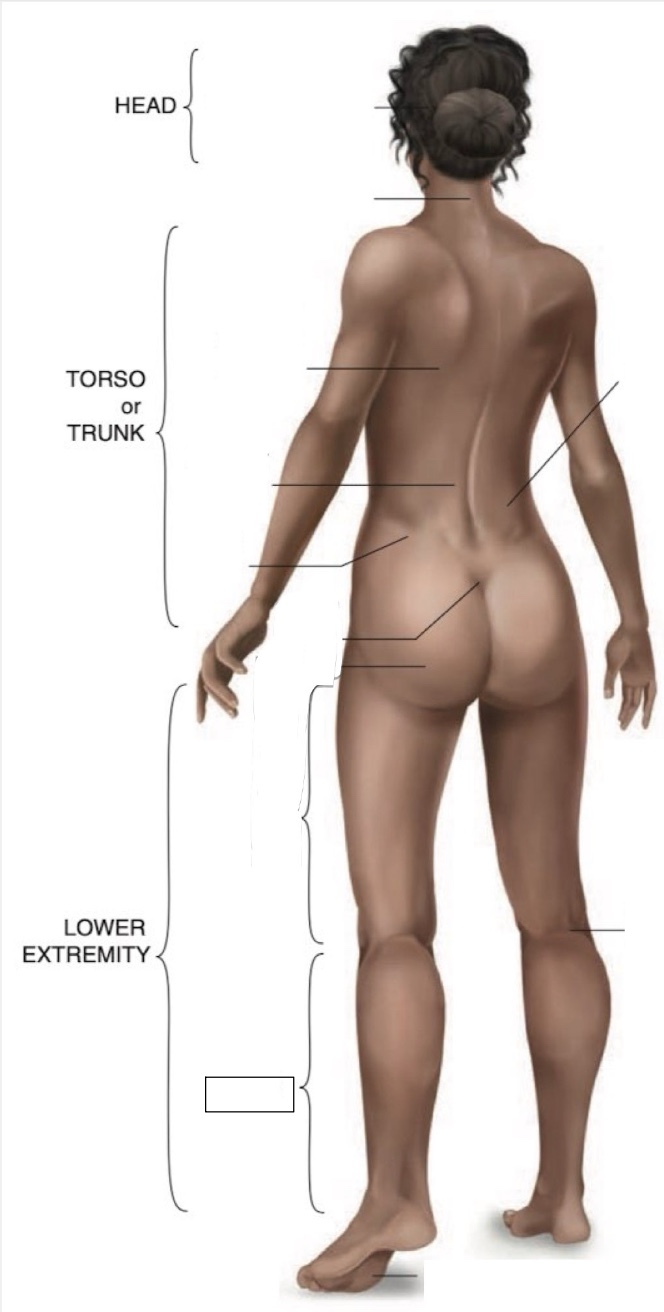

Occipital region

Cervical region

Inferior angle of scapula

Lumbar region

Iliac crest

Sacral region

Buttock

Thigh

Leg

Flank

Popliteal region